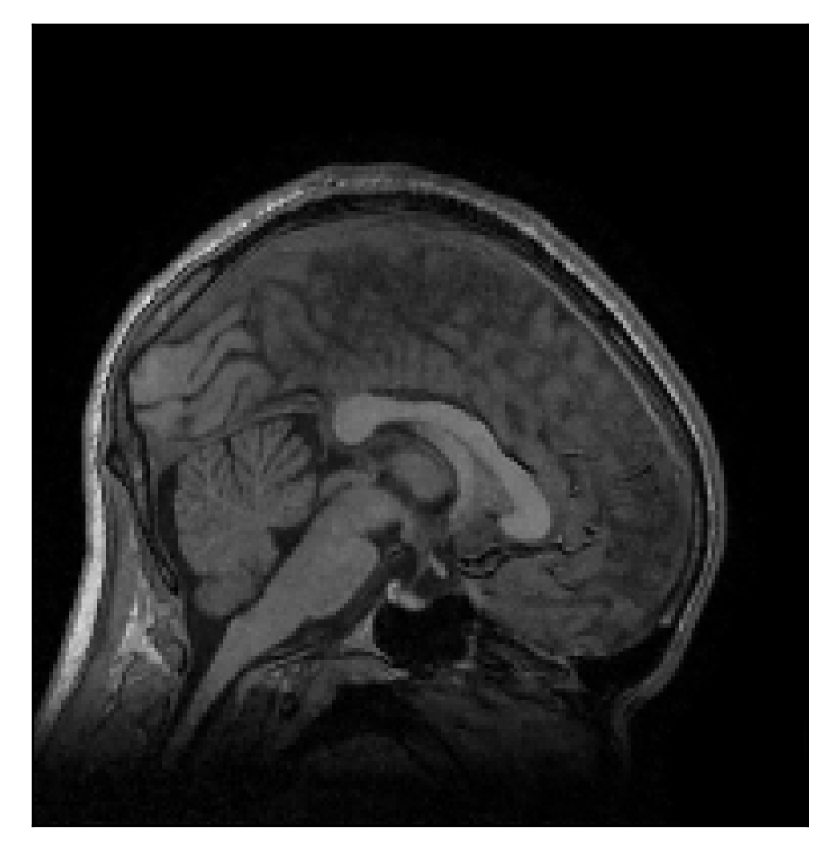

We consider three levels of motion corruption: (i) the volunteer moves once, (ii) the volunteer moves twice, and (iii) the volunteer moves five times. The volunteer is instructed to change its head position every time it is prompted to do so, and maintain that position in between instructions. We use T2-FLAIR-weighted contrasts as corrupted scans, with T1-weighted contrast as a reference (see Table 1 for further details). The corrupted acquisition employs randomized sampling.

| Section 3.1, Figure 2 | Sagittal | 23.94 | 27.95 | 0.7068 | 0.7936 |

| Coronal | 26.66 | 29.82 | 0.7653 | 0.8332 | |

| Axial | 25.40 | 30.16 | 0.7616 | 0.8490 | |

The motion-corrected full-volume scans were analyzed by a neuroradiologist with 16 years of experience. These were generally deemed of good radiological quality. The motion-related artifacts have been completely removed, and the results are quite close to the ground truth. In Table 3, we organized a more detailed qualitative analysis of the 3D results, geared toward a radiological assessment of the corrected scans.

| Experiment | Contrast | Motion resolution | Blurring | Artifacts | Additional comments |

| Section 3.1, Figure 2 | T2-FLAIR | Completely corrected | Some blurring | No additional artifacts | Good grey white matter differentiation |

4.1 Experiment 1: robustness test

We gather the results for the robustness test described in Section 3.1 (volunteer 1) in Figures 2, 4, and 6 for motion corruption mechanisms associated to one, two, and five changes of position, respectively. Furthermore, we juxtapose the corrected images with varying degrees of corruption in Figure 8. We observe that the proposed method consistently ameliorates the corrupted scan. The quality indexes based on PSNR and SSIM show only a modest decrease in correction quality as a function of motion complexity (Figure 8).

Our experimentation based on volunteer data aimed at assessing the robustness of the correction quality with respect to motion artifacts of increasing complexity. In this study, we equated this complexity to the number of volunteer changes of pose during the acquisition phase. Clearly, this does not fully describe the complexity of motion encountered in practice in the clinic, but it only constitutes a preliminary step in that direction. Nevertheless, the results described in Section 4.1 support the indication that the retrospective motion correction of T2-FLAIR weighted images based on a T1 reference contrast is quite robust in terms of reconstruction quality, with only minor degradations in terms of contrast and resolution.

Sagittal

Coronal

Axial

Axial detail